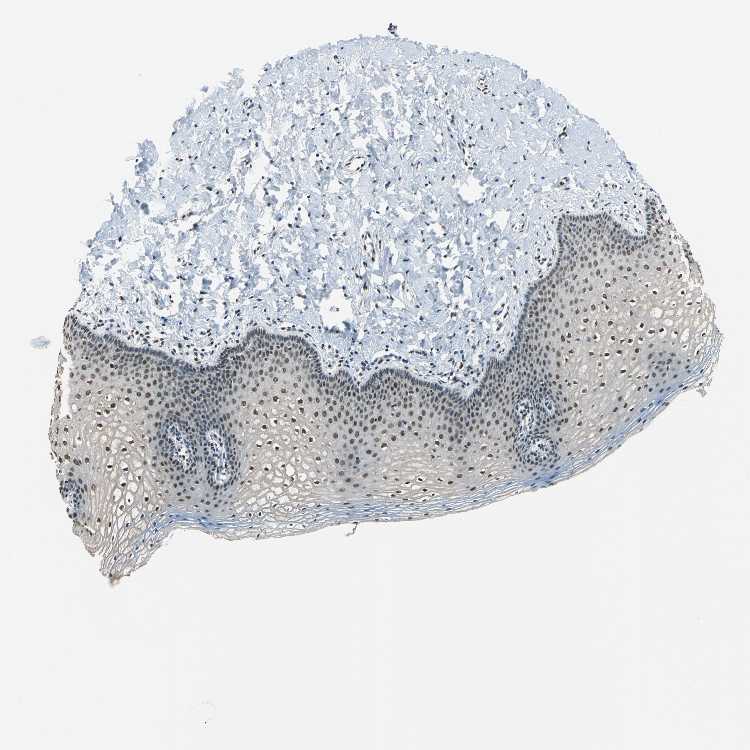

VAGINA - Antibody stainingi

Antibody staining in the annotated cell types in the current human tissue is reported as not detected, low, medium, or high, based on conventional immunohistochemistry profiling in selected tissues. This score is based on the combination of the staining intensity and fraction of stained cells.

Each image is clickable and will lead to virtual microscopy that enables deeper exploration of all samples and also displays staining intensity scores, fraction scores and subcellular localization as well as patient and tissue information for each sample.

Antibody HPA006628

Squamous epithelial cells Medium